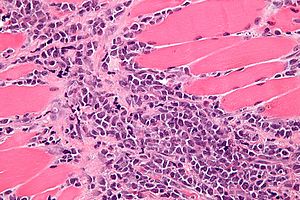

Chloroma. H&E stain. | |

| LM | atypical small blue cells ~2x resting lymphocyte, infiltrative |

- Cluster of atypical small blue cells in soft tissue with scant cytoplasm.